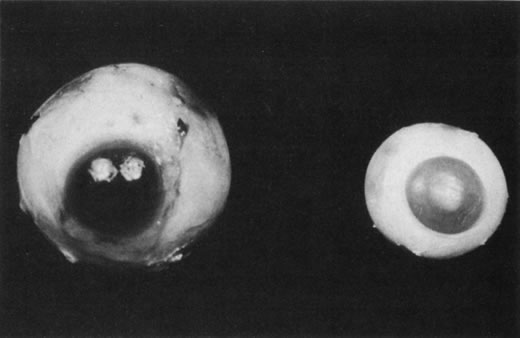

for the Classification of the Late Stages of Retinopathy of Prematurity. Arch Ophthalmol 105:906, 1987. 60a. Capone A Jr, Trese MT: Lens-sparing vitreous surgery for tractional stage 4A retinopathy

Group. Arch Ophthalmol 114:1085, 1996 62. Trese MT. Scleral buckling for retinopathy of prematurity. Ophthalmology 101:23, 1994 63. Hinz BJ, de Juan E Jr, Repka MX: Scleral buckling surgery for active stage 4A retinopathy of prematurity. Ophthalmology 105:1827, 1998 64. Chuang YC, Yang CM: Scleral buckling for stage 4 retinopathy of prematurity. Ophthalmic Surg Lasers 31:374, 2000 65. Choi MY, Yu YS: Efficacy of removal of buckle after scleral buckling surgery for retinopathy

repair. Ophthalmology 91:461, 1984 73. Hirose T, Katsumi O, Mehta MC, Schepens CL: Vision in stage 5 retinopathy of prematurity after retinal reattachment

by open-sky vitrectomy. Arch Ophthalmol111:345, 1993 74. Tasman W, Borrone RN, Bolling J: Open sky vitrectomy for total retinal detachment in retinopathy of prematurity. Ophthalmology 94:449, 1987 75. Clarkson JG, Jacobson SG, Frazier-Byrne S, Flynn JT: Evaluation of eyes with stage-5 retinopathy of prematurity. Graefes Arch Clin Exp Ophthalmol 227:332, 1989. 76. Trese MT: Surgical therapy for stage V retinopathy of prematurity. A two-step

approach. Graefes Arch Clin Exp Ophthalmol 225:266, 1987 77. Schepens CL: Clinical and research aspects of subtotal open-sky vitrectomy. XXXVII Edward Jackson Memorial Lecture. Am J Ophthalmol 91:143, 1981 78. Hirose T, Schepens CL, Lopansri C: Subtotal open-sky vitrectomy for severe retinal detachment occurring